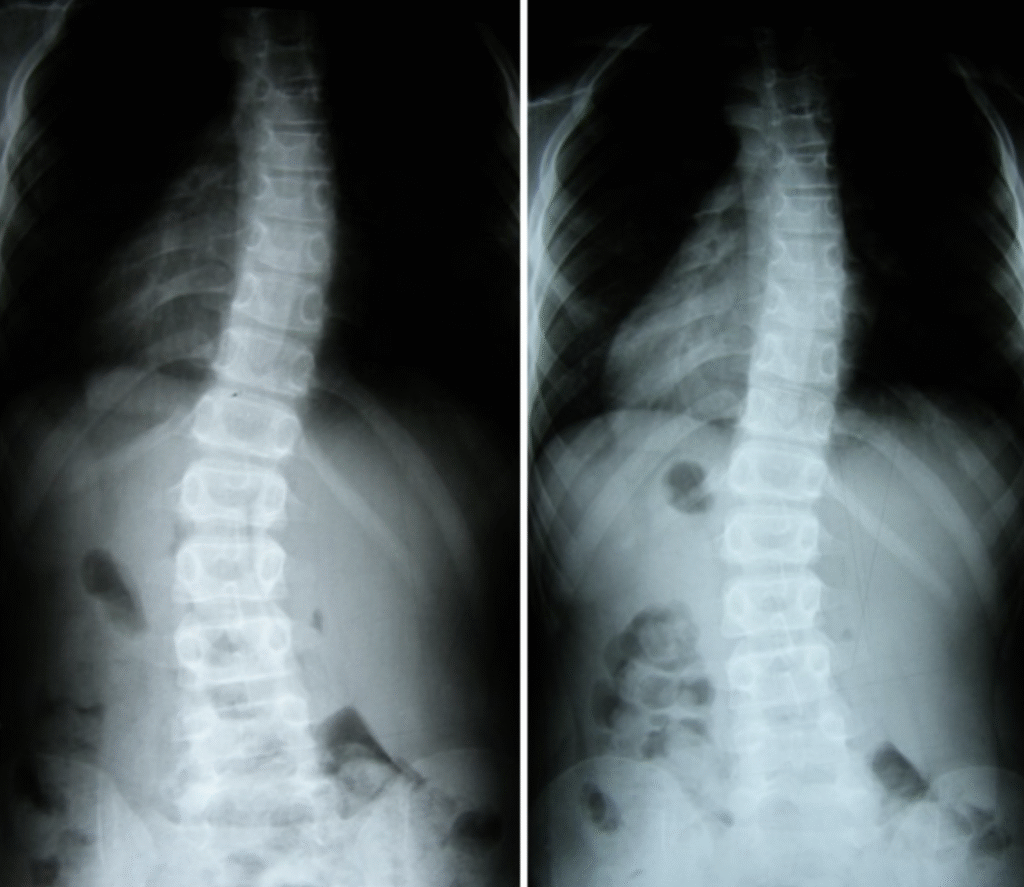

Piotr – 10 lat

Terapia prowadzona w okresie 15.09 – 01.12.2008 (20 zabiegów) Częstotliwość zajęć – 2 x tydz.

Justyna – 15 lat

Terapia prowadzona w okresie 02.08.2010 – 06.04.2011 (40 zabiegów) Częstotliwość zajęć – 2 x tydz.